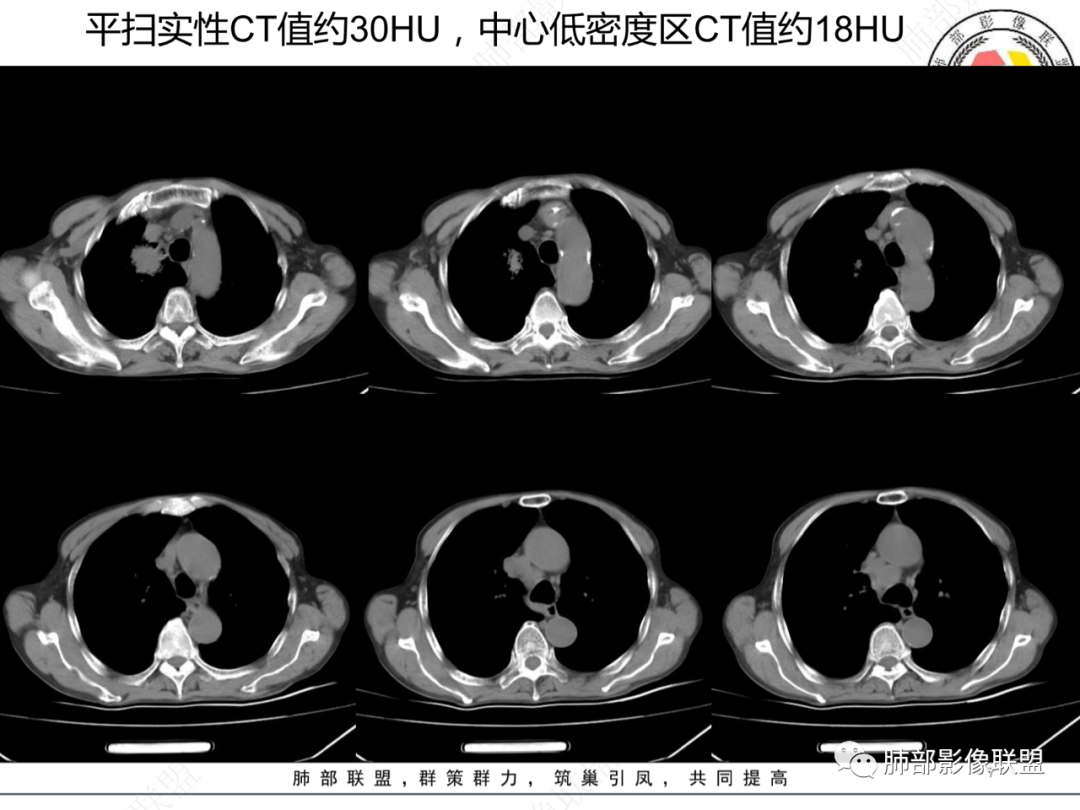

这个病例,第一次增强,发现里面结构扭曲,强化不是很显著,直接报了肺癌。

最后还是考虑鳞癌

患者有高血压、脑梗死、肾结石病史,因左胸痛不适入院,伴高热,血常规示白细胞、中性粒细胞高。胸部CT示右肺上叶肿块影,边缘模糊影,内可见低密度坏死,边界清楚,一月后出现气液平面,周围渗出,治疗2周复查液平及周围炎症吸收,肿块未见明显吸收。

考虑肿瘤?右肺上叶高密度影,边缘模糊,侵及纵隔及胸廓入口,病灶密度不均匀,部分支气管截断,增强后不均匀强化,内可见较大范围坏死,纵隔多发肿大淋巴结不均匀强化。肺上沟瘤不能排除。

感染性病变?右肺上叶尖段团块影,中央见大片状状坏死伴液气平面,周围见斑片状高密度影,实验室检查血象明显升高,抗炎治疗后,病灶有所吸收缩小,灶周斑片状消失。